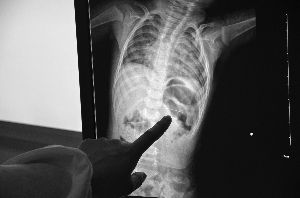

X光片里,绣花针完全扎进左肾,取出后已断成两截

烁烁被连夜送到常州市儿童医院,经进一步检查发现,细长的绣花针已贯穿他的左侧肾脏。

1月11日上午,医生为小烁烁实施了手术,取出了一根长约3.5厘米的绣花针。

“绣花针能扎入这么深,确实少见,一般来说,即使不小心扎到孩子,也只会刺入皮下组织或者肌肉,但现在基本上整根针都插进了左肾。”小儿外科副主任医师黄岭竹说,从刺入的角度接近90度和深度来看,不排除人为刺入的可能,但这个需要警方调查。另外,医生发现从烁烁体内取出的绣花针针鼻子(针尾的小孔,用于穿线)已经断裂,断裂部分至今还没找到,CT检查也没有发现孩子体内留有金属物质。